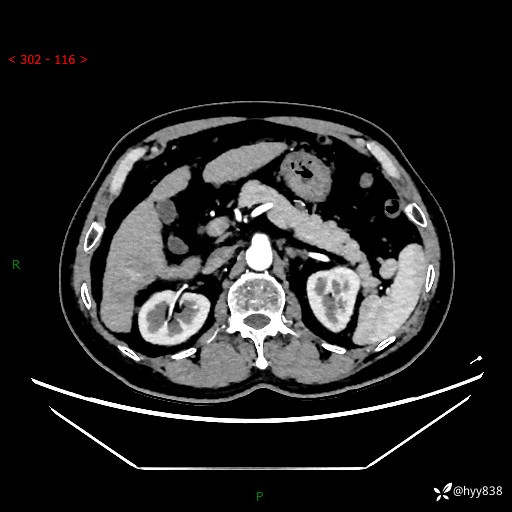

静脉期